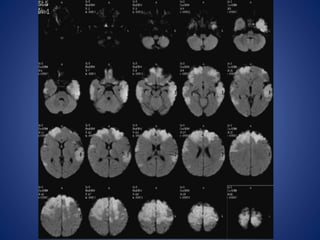

• 7 yr old girl, with sudden onset of severe right sided headache, followed

by left hemiparesis & slurred speech of one day duration.

• H/o Chickenpox 2 months back.

13 yrs male, with history of seizures with cilinical suspicion of febrile

encephalitis.

DWI

ADC

IR